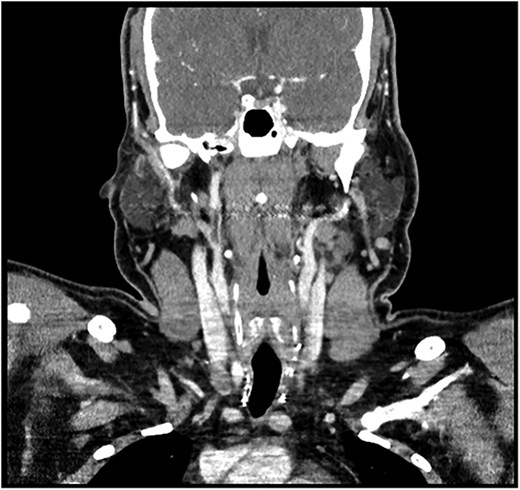

A 28-year-old man with a BMI of 44.3 kg/m2 and, a history of hypertriglyceridemia on gemfibrozil 600 mg complained of neck swelling for 2 years. It began as a nodular swelling at the right supraclavicular region and later spread to the right axillary and left supraclavicular areas. For one month, the patient had an unintentional weight loss of 4 kg and a few episodes of night sweats but no fatigue, fever, or compressive symptoms. He never received any radiation treatment. The family history was positive for an aunt with a malignant thyroid disease, for which she had a total thyroidectomy done. He was also on calcium carbonate 1200 mg orally thrice daily and levothyroxine 200 mcg orally once daily. On general examination, the patient did not look dehydrated, the patient was afebrile and did not appear to be in acute respiratory distress. There was a firm, nontender, nonmobile mass in the right anterior neck which represents lower cervical lymphadenopathy. No thyroid nodules, thrills, or shift of the trachea to the right were found. Abdominal examination was normal, that is, no enlargement or tender masses were felt on abdominal palpation. It started in January 2018 with right sided lymph node enlargement and a detailed assessment was done at a hospital in the United Kingdom (UK) in March 2020. FNA of the neck nodes showed features of HL and the thyroid US showed a hypoechoic nodule with punctate calcifications measuring 3.9 × 1.9 cm and TI-RADS 5. Other findings were bilateral clinically suspicious cervical lymphadenopathy; the largest nodes being 3.6 × 2 cm on the right side and 2.8 × 1.3 cm on the left side. The laboratory findings included T3 of 5.19 pmol/L, T4 of 25 pmol/L, and thyroid stimulating hormone (TSH) of 0.817μIU/ml. According to these observations, the patient underwent further investigations and imaging, CT of the chest revealed necrotic mediastinal, bilateral axillary, and subpectoral lymph nodes suggesting intrathoracic metastases most probably from PTC or lymphoma (Fig. 1). A nuclear medicine scan confirmed FDG-avid disease in the thyroid and nodal areas above the diaphragm. A subsequent FNA of the thyroid nodule revealed papillary thyroid carcinoma (Fig. 2). The patient had a total thyroidectomy, central compartment lymph node dissection, and excision in March 2020. Surgical pathology showed PTC in the right thyroid lobe measuring 2.5 cm in diameter and ipsilateral cervical lymph node involvement. The postoperative treatment included radioactive iodine ablation of 120 mCi in December 2020, and thyroglobulin level was negative. However, the patient got other symptoms by November 2023 after the above-mentioned interventions were conducted. Postoperative US of the neck, done after thyroidectomy, did not demonstrate any thyroid tissue but multiple enlarged cervical lymph nodes, including one that was 2.3 × 1.2 cm in size, with some of the nodes matted and non-encapsulated with loss of fatty hilum. CT imaging revealed an interval increase in the size of right cervical and supraclavicular LN (Fig. 3) and nuclear imaging showed relapsed HL with FDG-avid lymph nodes, above and below the diaphragm. The histopathological examination of the right cervical lymph node excisional biopsy was done and immunohistochemistry staining of markers compatible with CHL was observed (Figs 4 and 5). The tumor cells were positive for CD 30, CD 15 (partially), MUM 1, and PAX 5 (faintly), and the reactive lymphocytes for CD 3 only. The diagnosis of relapse of classical Hodgkin lymphoma (CHL) called for additional oncologic assessment and intervention.

Bilateral enlarged and necrotic left intraparotid, cervical, and supraclavicular lymph nodes.